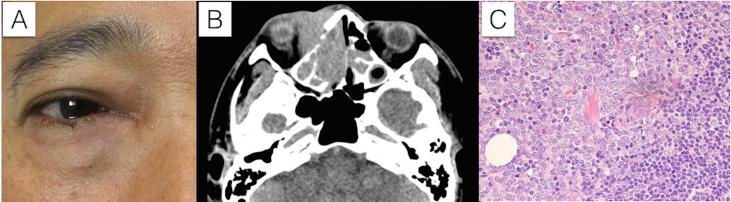

To describe an orbital myeloid sarcoma in adult presenting with a swollen mass at inferomedial canthal area and epiphora which was misdiagnosed as nasolacrimal duct obstruction.

A 45-year-old male presented with a swollen right lower eyelid around medial canthal area for 2 months with tearing for 6 month-period earlier. Eye examination demonstrated a high tear meniscus, slightly erythematous eyelid with palpable mass closed to the lacrimal sac along the inferior orbital rim. Computed tomography scan depicted infiltrative mass at the inferomedial aspect of right orbit with bony erosion, extended to adjacent paranasal sinuses. An incisional biopsy was performed. Histopathological study revealed soft tissue which was diffusely infiltrated by monotonous medium-sized round cells resembling blasts with lymphoglandular bodies, focally positive myeloperoxidase and negative lymphoid markers. The findings were consistent with myeloid sarcoma. No systemic involvement was found. The patient underwent chemotherapy and radiation without systemic leukemic disease progression.

一名45岁男性,右内眦部周围下眼睑肿胀2个月,此前有6个月的流泪症状。眼部检查发现泪液弯月面较高,眼睑轻度红斑,沿眶下缘在泪囊附近可触及肿块。计算机断层扫描显示右眼眶内下侧有浸润性肿块,伴有骨质侵蚀,并延伸至相邻鼻窦。进行了切开活检。组织病理学研究显示软组织被单一的中等大小圆形细胞弥漫浸润,这些细胞类似原始细胞,伴有淋巴腺小体,髓过氧化物酶局部阳性,淋巴样标记物阴性。这些发现符合髓系肉瘤。未发现全身受累。患者接受了化疗和放疗,未出现全身性白血病进展。